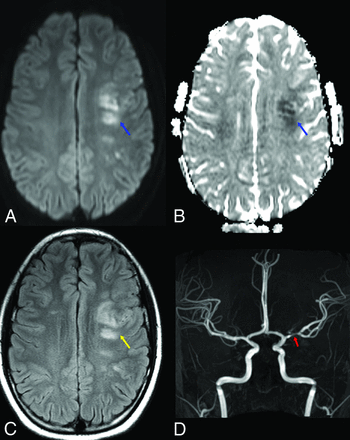

COVID-19-associated left MCA vascular territory acute infarcts in a pediatric patient. Axial diffusion (A), ADC map (B), and FLAIR (C) images demonstrate foci of restricted diffusion (blue arrows) and cytotoxic edema (yellow arrow) within the left middle cerebral artery vascular territory, consistent with acute infarcts. Anterior projection from a TOF-MRA of the head (D) demonstrates a focal segment of moderate stenosis within the left M1 middle cerebral artery (red arrow).